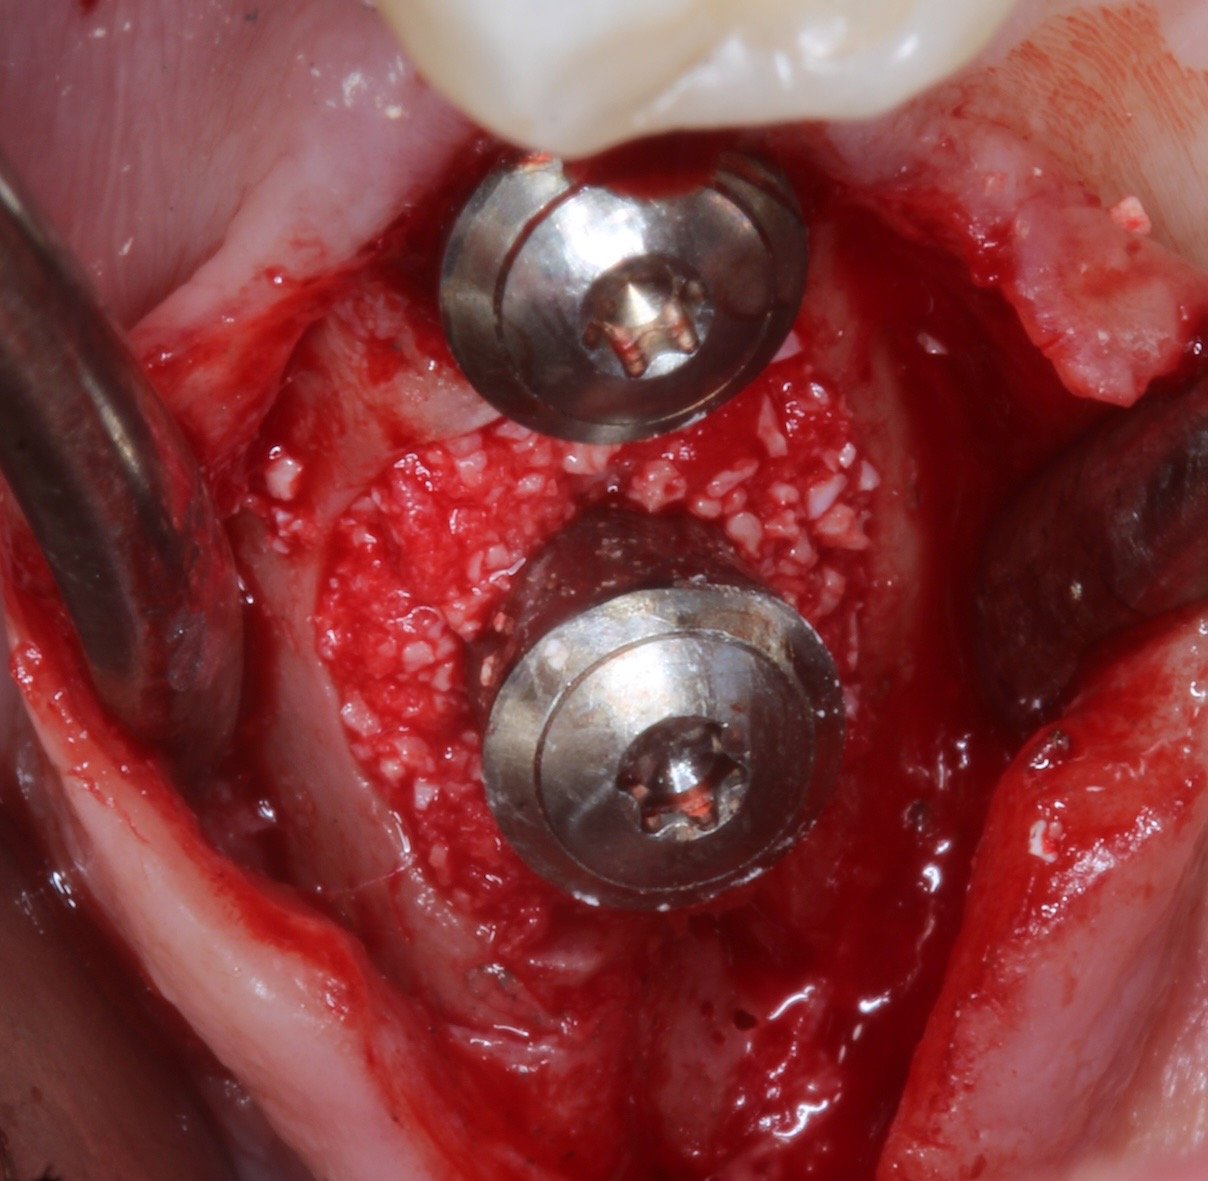

Le traitement chirurgical de la péri-implantite constitue aujourd’hui un enjeu majeur en implantologie pour assurer la pérennité des traitements et la satisfaction des patients.

Cette formation DPC, interactive et clinique, vous permettra de maîtriser les protocoles chirurgicaux les plus récents pour contrôler l’infection et stabiliser les tissus péri-implantaires. À travers des situations réalistes et des analyses radiographiques, vous serez guidé pas à pas pour transposer les recommandations scientifiques dans votre pratique quotidienne.

Connaître et appliquer les différentes approches chirurgicales (résectrices, régénératrices et combinées).